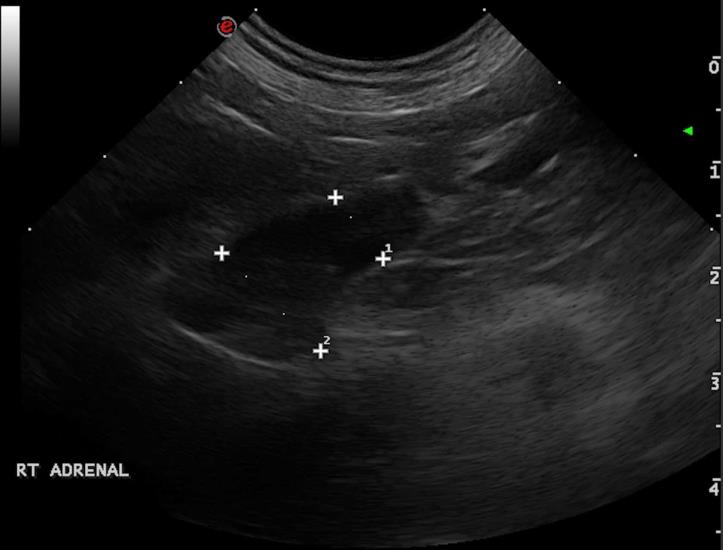

A 8-year-old cocker spaniel was referred for polyuria/polydipsia and polyphagia. The abdominal ultrasound revealed bilateral symmetric adrenal enlargement (images below). A CT scan of the head was performed. A round, 7mm, contrast-enhancing nodule was found at the level of the pavement of the sella turcica, in the hypophyseal fossa (green arrowheads).